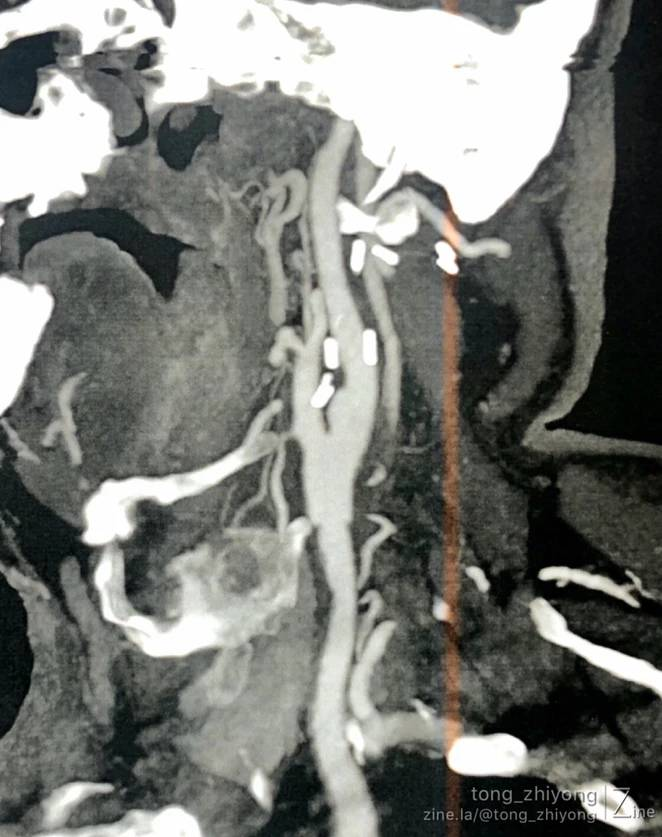

CTA确认:支架内重度再狭窄;

CTA确认:支架上端位于C2锥体上缘;颈内动脉内释放的6mm支架的直径“大于”远心端颈内动脉的直径。

显露到支架远心端颈内动脉,确认:颈内动脉内释放的6mm支架的直径“大于”远心端颈内动脉的直径。

术后一周CTA显示:颈部操作最上端到达C1锥体水平。钛结扎夹在CTA上像“香米粒”一样。

完全开通左侧颈动脉